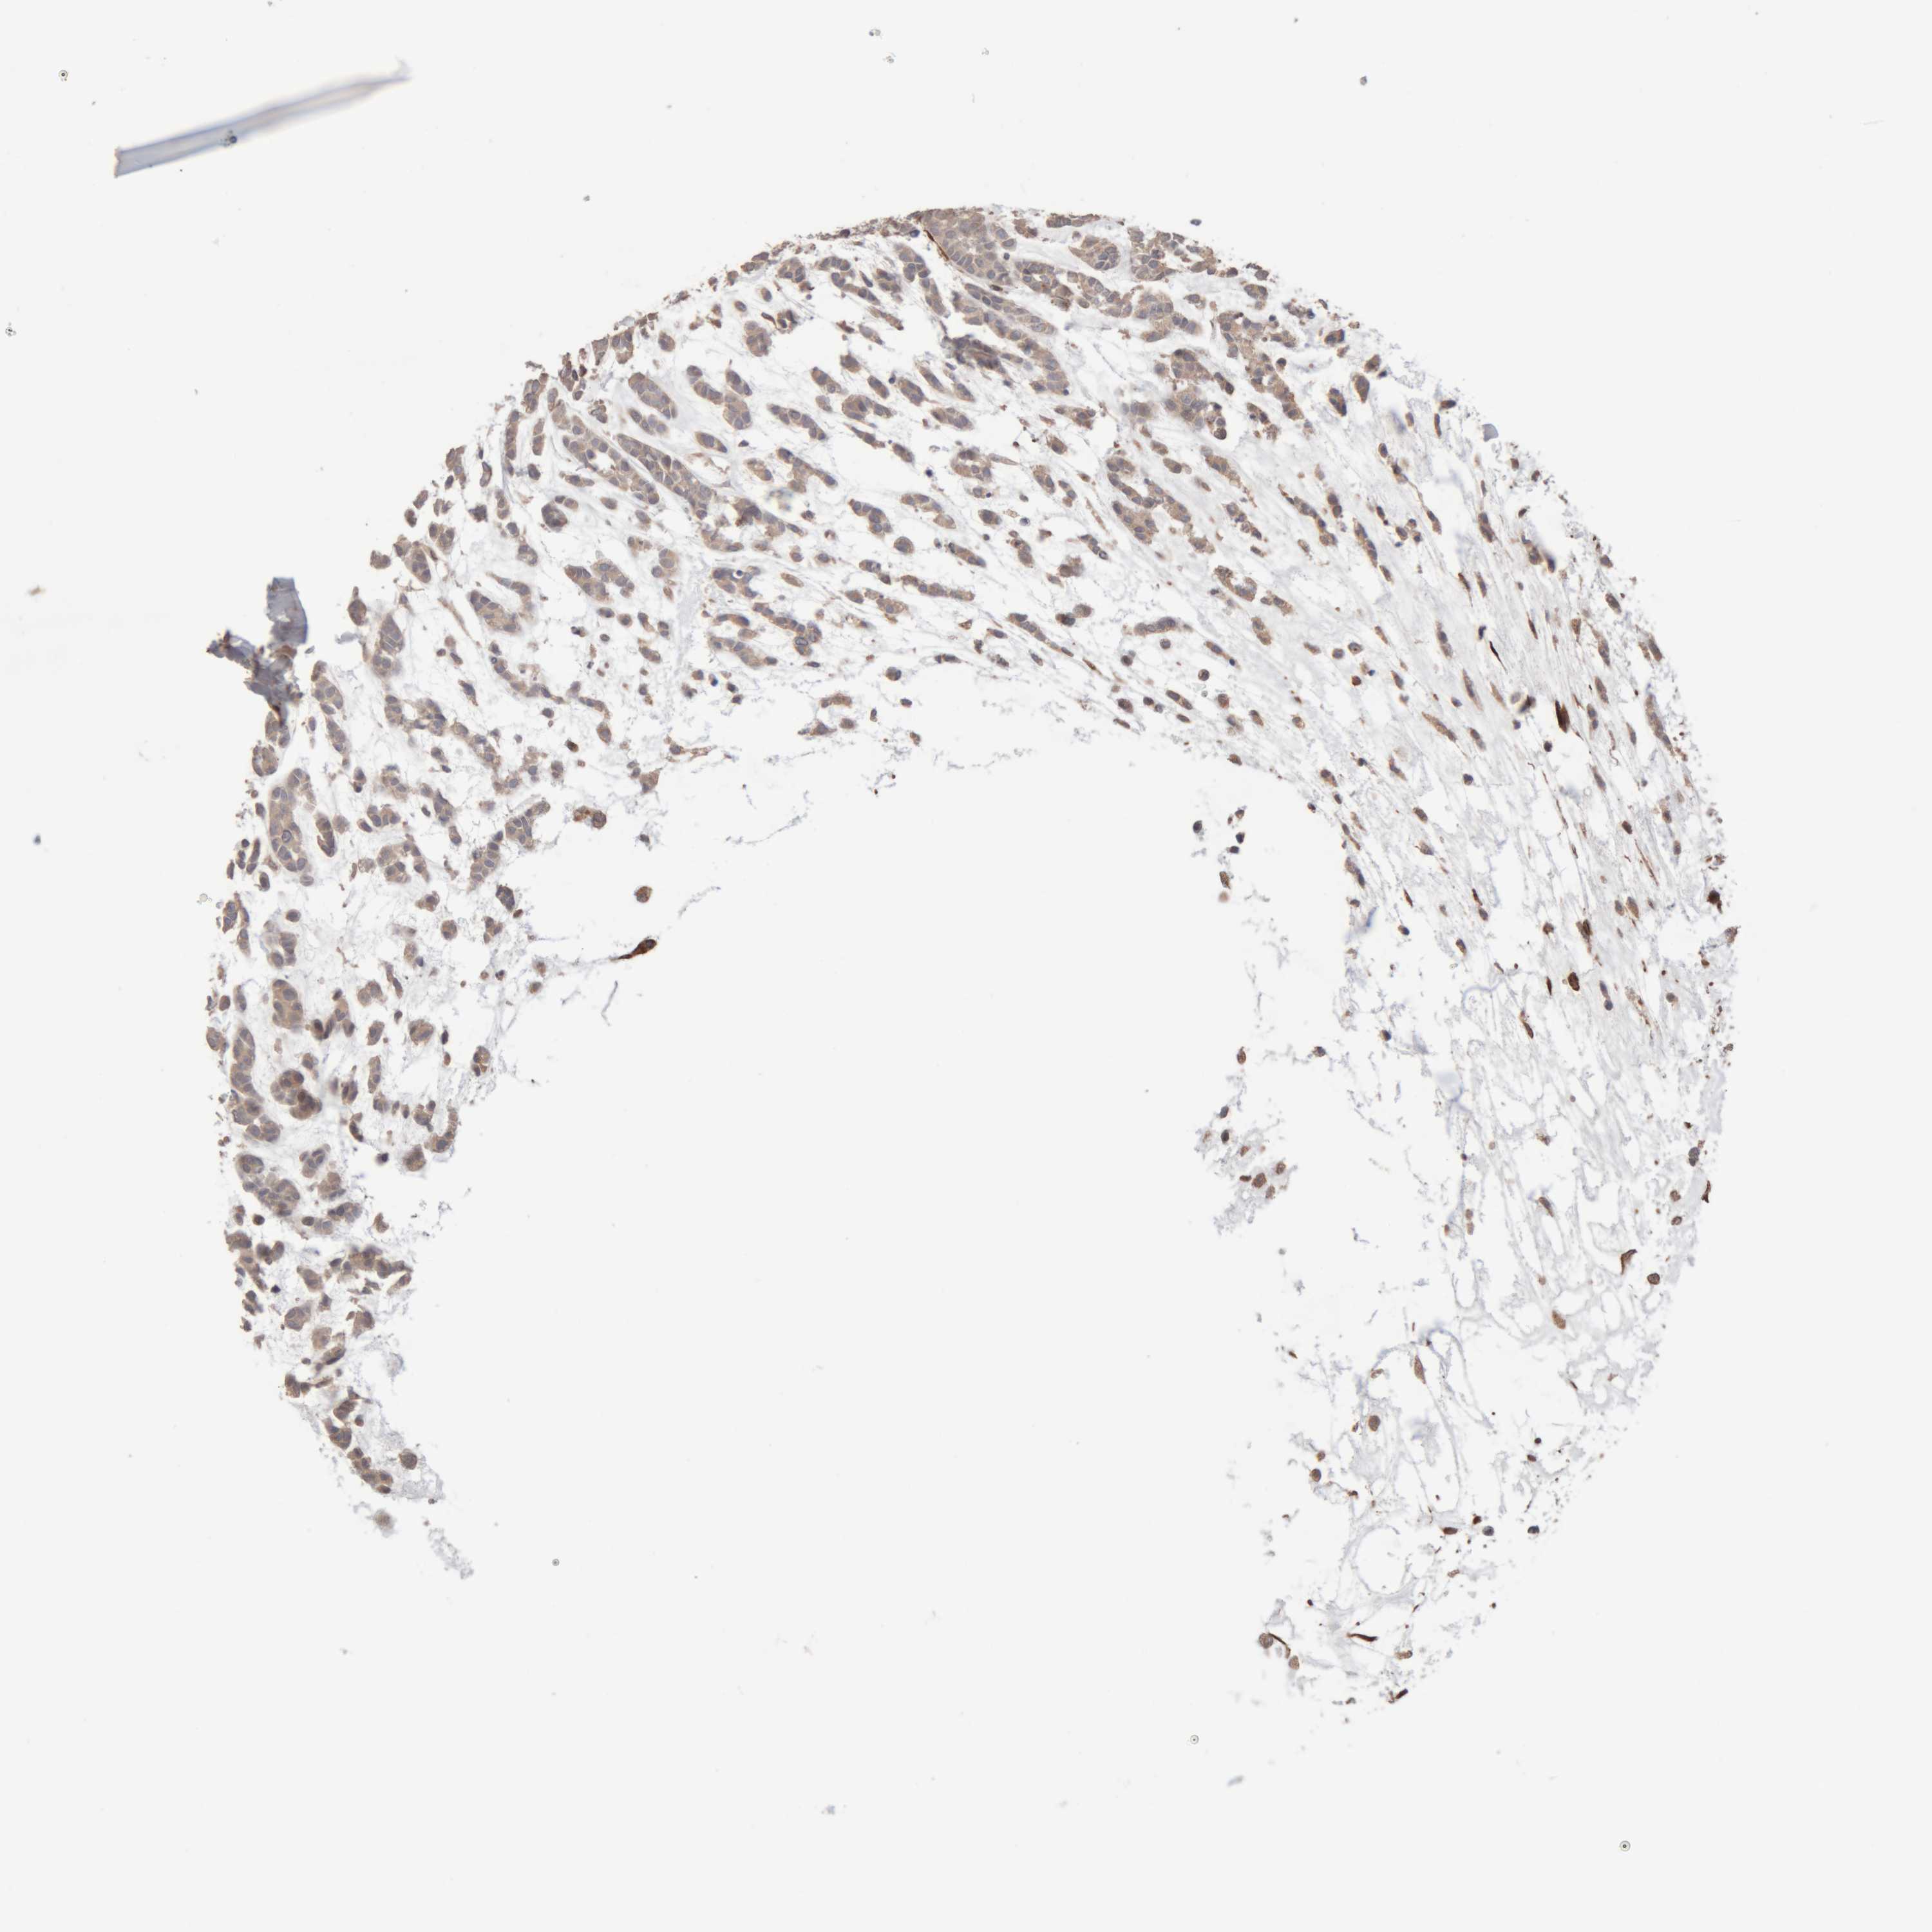

HEAD AND NECK CANCER - Protein expressioni

A mouse-over function shows sample information and annotation data. Click on an image to view it in a full screen mode. Samples can be filtered based on level of antibody staining by selecting one or several of the following categories: high, medium, low and not detected. The assay and annotation is described here.

Antibody stainingi

Antibody staining in the annotated cell types in the current human tissue is reported as not detected, low, medium, or high, based on conventional immunohistochemistry profiling in selected tissues. This score is based on the combination of the staining intensity and fraction of stained cells.

Each image is clickable and will lead to virtual microscopy that enables deeper exploration of all samples and also displays staining intensity scores, fraction scores and subcellular localization as well as patient and tissue information for each sample.

Antibody HPA025731

Staining

High

Medium

Low

Not detected

Intensity

Strong

Moderate

Weak

Negative

Quantity

>75%

75%-25%

<25%

None

Location

Nuclear

Cytoplasmic/membranous

Cytoplasmic/membranous,nuclear

Squamous cell carcinoma, NOS

Squamous cell carcinoma, metastatic, NOS

Adenocarcinoma, NOS

Adenoma, NOS